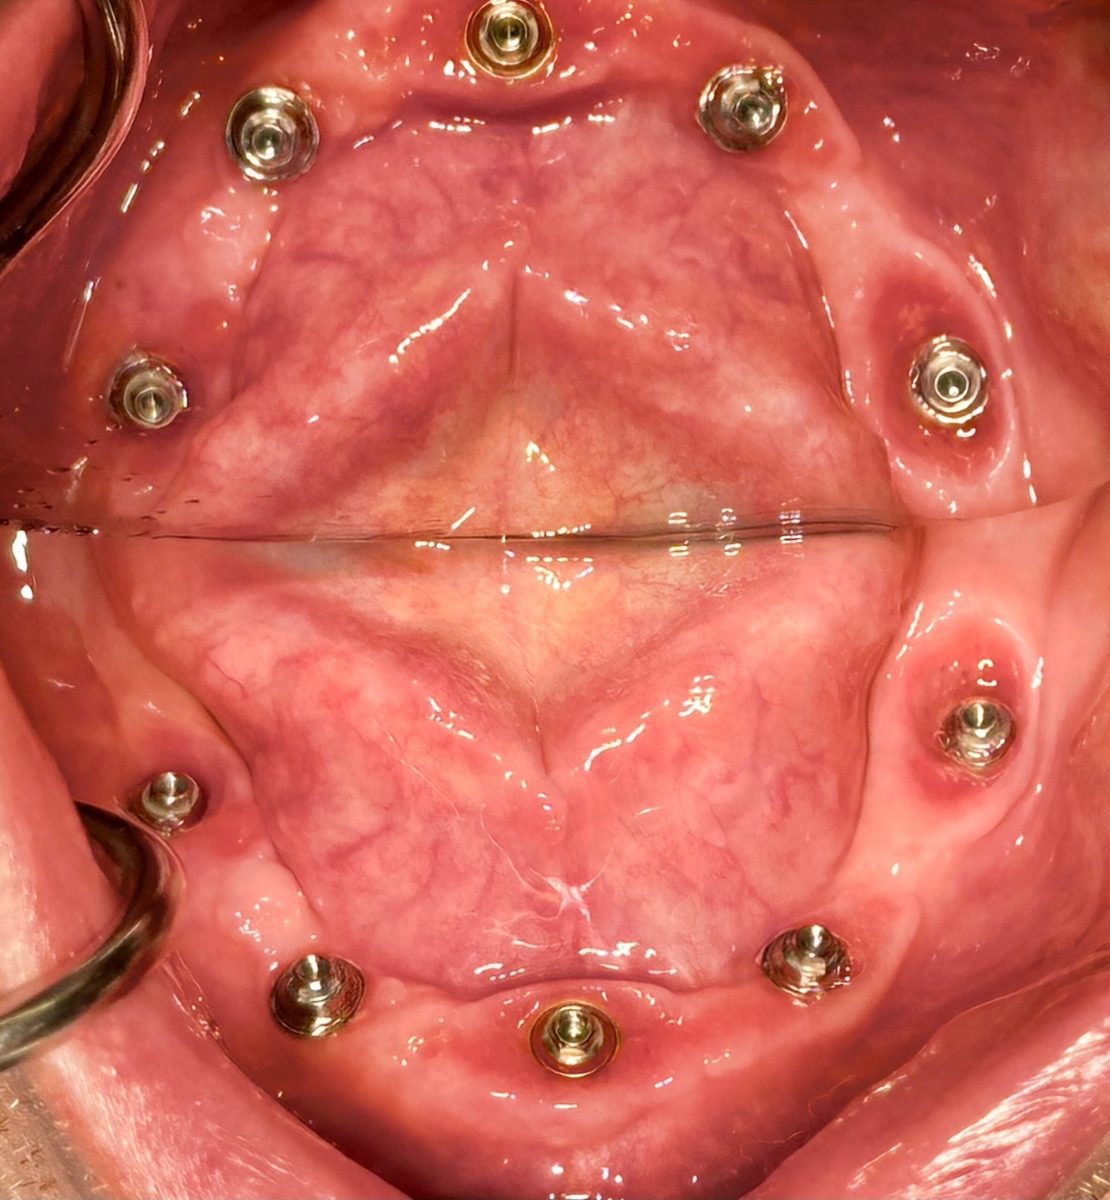

Implants placed using a digitally planned stackable surgical guide following alveolectomy, ensuring ideal positioning and a stable foundation for full-arch restoration.